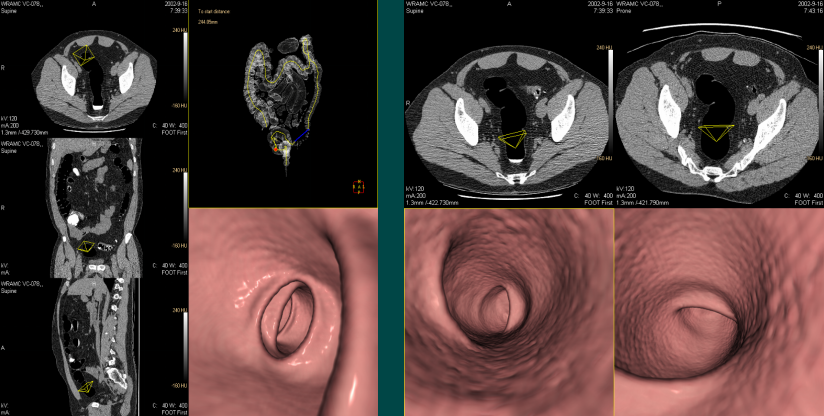

结肠CAD(虚拟内窥)

虚拟内窥功能包括沿着中心线方向的虚拟自动漫游,以及手动漫游。

结肠CAD(虚拟切开)

结肠虚拟切开包括“立方体虚拟切开”来显示360 度的三维全景和切开在一个平面上显示的整个结肠二维全景。